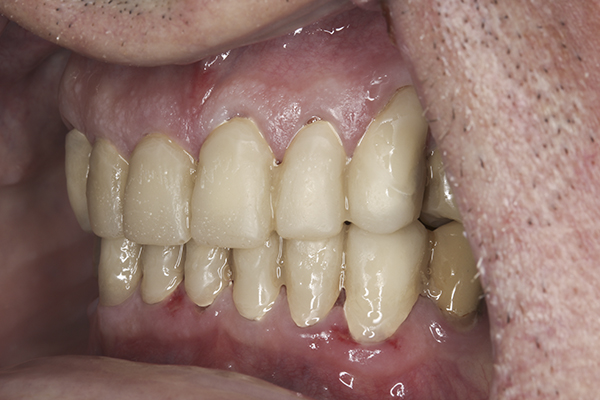

(35.) Postoperative right lateral, closed view.

Figure 35

(36.) Postoperative anterior, closed view. Note the position of the upper and lower canines to provide canine guidance.

Figure 36

(37.) Postoperative left lateral, closed view.

Figure 37